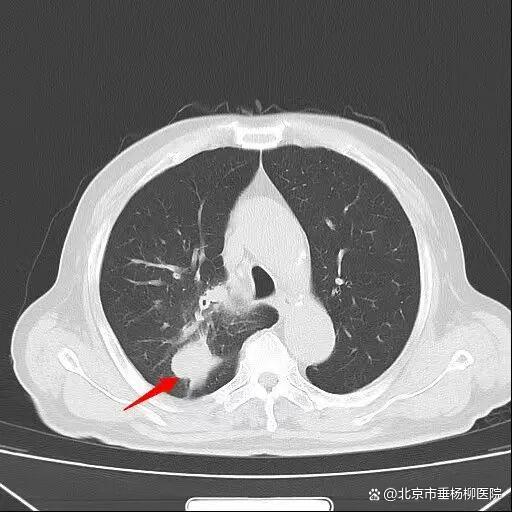

患者王大爷一年前体检发现右肺上叶有一约6×4mm结节,当时未予重视。一年后,他突然出现活动后喘憋症状,复查胸部CT显示右肺上叶后段出现约50×50mm不规则实性团块,影像学高度怀疑肺恶性肿瘤。

入院后,胸外科团队为患者行超声引导下经支气管针吸活检(EBUS-TBNA),病理结果提示为小细胞癌,并发现纵隔淋巴结转移。进一步全身检查显示,患者已出现肋骨及肝内多发转移,诊断为右肺上叶小细胞肺癌(cT3N2M1c IVB期)。

经过一个周期的治疗后,患者喘憋、咳嗽等呼吸道症状明显缓解,复查影像显示右肺上叶肿物显著缩小,疗效评估良好。这一结果让患者及家属重拾治疗信心,也为下一阶段治疗奠定了基础。